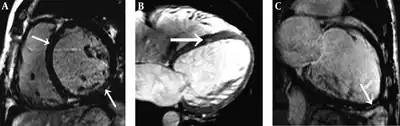

| Individual with a diffuse form of Keshan disease a) Short-axis, b) four-chamber c)long-axis delayed-enhancement | |